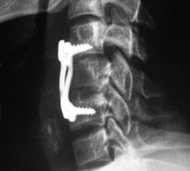

- Рентгенографію. Медпрацівники зазвичай проводять рентгенографію всім травмованим, у кого є підозра на пошкодження спинного мозку. Рентген може виявити проблеми з хребцями, пухлини, переломи або дегенеративні зміни в хребті.

Мета операції - стабілізація хребта металевими конструкціями (імплантантами). Наша клініка була першою в СНД, яка застосувала сучасні конструкції при переломах хребта. Нині ми використовуємо імпортні конструкції типу CD Horison Legacy (США), Atlantis (США), Sextant (США), Socore (Франція). Операції вимагають складної рентгенівської техніки та спеціального інструментарію. При неускладнених переломах хребта хворі можуть ходити після таких операцій уже на другий - третій день. Також в Міжнародному центрі нейрохіургіі вперше в Україні впроваджено метод мініінвазивних операцій при переломах хребта.